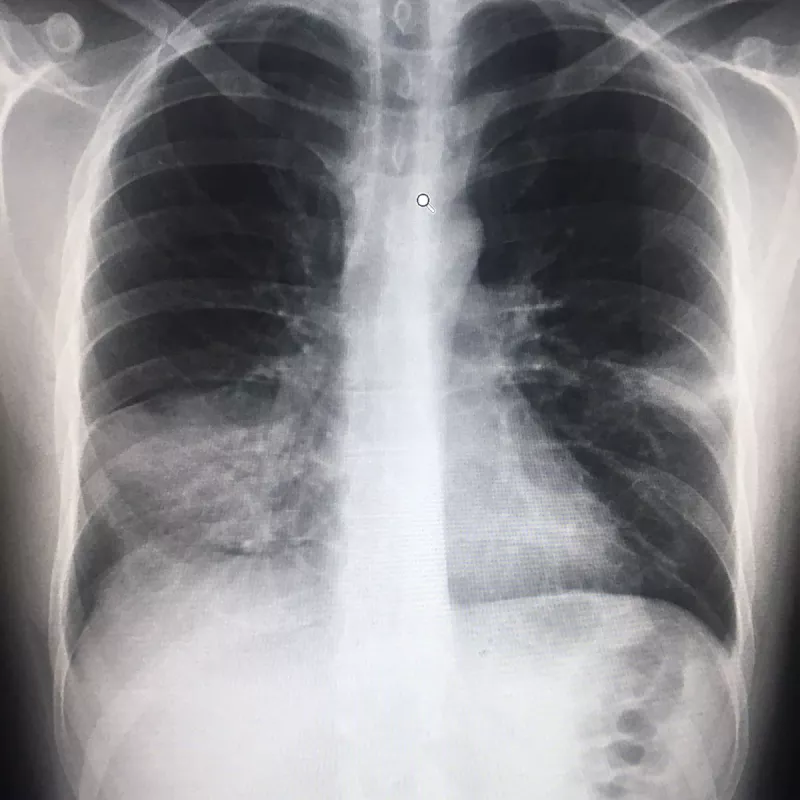

xray

The next bit unfolded like a dream. I was given some drips. The wheelchair man pushed me along to the X-ray department. “You have pneumonia, a nasty one,” a doctor said. A few hours and four infusions later, I was given a box of antibiotics and sent on my way. The choreography was truly impressive. I’m glad I was taking the drugs before the next episode: when I started coughing blood. At least I was taking something, and over a few days felt much better.

I joked with my doctor friend, the one I messaged, that he’d been careless telling me not to see my doctor. His reaction was along the lines of, ‘Well you’re still alive, aren’t you?’ But, as an afterthought, he asked to look at my x-ray himself, in case he could recommend a follow-up check. A few days later with no news, I gave him a call.

“Oh, yeah,” he said. “You’re fine. You have very sexy lungs.”